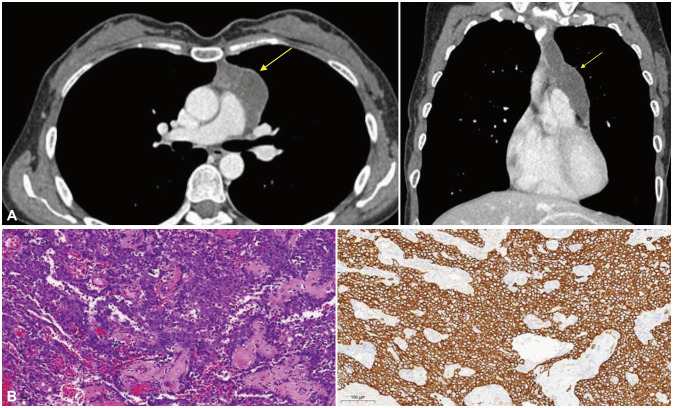

Stiff-Person Syndrome Associated With Metastatic Thymoma.

Abstract Image